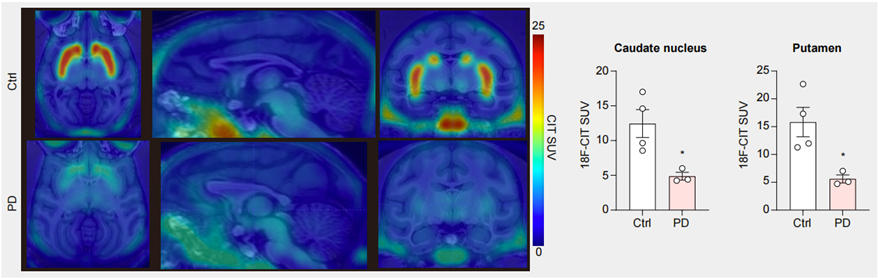

● 分子影像數(shù)據(jù)展示造模后,動物腦內(nèi)多巴胺神經(jīng)元損傷;

圖3. PET-CT結(jié)果顯示PD模型猴腦中多巴胺神經(jīng)元減少